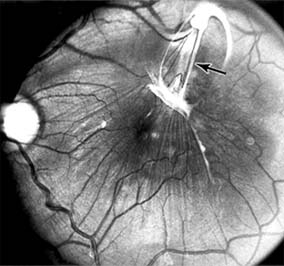

Chapter 10: Retina DISEASES OF THE MACULA AGE-RELATED MACULAR DEGENERATION Age-related macular degeneration is the leading cause of permanent blindness in the elderly. The exact cause is unknown, but the incidence increases with each decade over age 50. Other associations besides age include race (usually Caucasian), sex (slight female predominance), family history, and a history of cigarette smoking. The disease includes a broad spectrum of clinical and pathologic findings that can be classified into two groups: nonexudative ("dry") and exudative ("wet"). Although both types are progressive and usually bilateral, they differ in their manifestations, prognosis, and management. The more severe exudative form accounts for approximately 90% of all cases of legal blindness due to age-related macular degeneration. 1. NONEXUDATIVE MACULAR DEGENERATION Nonexudative age-related macular degeneration is characterized by variable degrees of atrophy and degeneration of the outer retina, retinal pigment epithelium, Bruch's membrane and choriocapillaris. Of the ophthalmoscopically visible changes in the retinal pigment epithelium and Bruch's membrane, drusen are the most typical (Figure 10-1). Drusen are discrete, round, yellow-white deposits of variable size beneath the pigment epithelium and are scattered throughout the macula and posterior pole. With time, they may enlarge, coalesce, calcify, and increase in number. Histopathologically, most drusen consist of focal collections of eosinophilic material lying between the pigment epithelium and Bruch's membrane; they therefore represent focal detachment of the pigment epithelium. In addition to drusen, clumps of pigment irregularly dispersed within depigmented areas of atrophy may progressively appear throughout the macula. The level of associated visual impairment is variable and may be minimal. Fluorescein angiography demonstrates irregular patterns of retinal pigment epithelial hyperplasia and atrophy. Electrophysiologic testing in most patients is normal. There is no generally accepted treatment or means of prevention of this type of macular degeneration. Laser retinal photocoagulation appears to have a beneficial effect on drusen but has not yet been shown to improve visual outcome. Although high plasma levels of antioxidants are associated with a reduced risk of age-related macular degeneration, the use of vitamin supplements does not appear to be preventive. Most patients with macular drusen never experience significant loss of central vision; the atrophic changes may stabilize or progress slowly. However, the exudative stage may develop suddenly at any time, and in addition to regular ophthalmic examinations, patients are given an Amsler grid ( 2. EXUDATIVE MACULAR DEGENERATION Although patients with age-related macular degeneration usually manifest nonexudative changes only, the majority of patients who experience severe vision loss from this disease do so from the development of subretinal neovascularization and related exudative maculopathy. Serous fluid from the underlying choroid can leak through small defects in Bruch's membrane, causing focal detachment of the pigment epithelium. Additional fluid may lead to further separation of the overlying sensory retina, and vision usually decreases if the fovea is involved. Retinal pigment epithelial detachments may spontaneously flatten, with variable visual results, and leave a geographic area of depigmentation at the involved site. Ingrowth of new vessels from the choroid into the subretinal space is the most important change that predisposes patients with drusen to macular detachment and irreversible loss of central vision. These new vessels grow in a flat cartwheel or sea-fan configuration away from their site of entry into the subretinal space. The clinical changes of early subretinal neovascularization are subtle and may be easily overlooked; during this occult stage of new vessel formation, the patient is asymptomatic, and the new vessels may not be apparent either ophthalmoscopically or angiographically. The ophthalmologist must maintain a high index of suspicion that subretinal neovascularization is present whenever a patient with evidence of age-related macular degeneration has sudden or recent central vision loss, including blurred vision, distortion, or a new scotoma. If the fundus examination reveals subretinal blood, exudate, or a grayish-green choroidal lesion in the macula, there is great likelihood that neovascularization is present, and a fluorescein or indocyanine green angiogram should be obtained promptly to determine if a treatable lesion can be identified. Although some subretinal neovascular membranes may spontaneously regress, the natural course of subretinal neovascularization in age-related macular degeneration is toward irreversible loss of central vision over a variable period of time. The sensory retina may be damaged by long-standing edema, detachment, or underlying hemorrhage. Furthermore, a hemorrhagic detachment of the retina may undergo fibrous metaplasia, resulting in an elevated subretinal mass called a disciform scar. This elevated fibrovascular mound of variable size represents the cicatricial end stage of exudative age-related macular degeneration. It is usually centrally located and results in permanent loss of central vision. Treatment In the absence of subretinal neovascularization, no medical or surgical treatment of serous retinal pigment epithelial detachment is of proved benefit. The use of parenteral alpha interferon, for example, has not been effective for this disease. However, if a well-defined extrafoveal ( Krypton laser photocoagulation of juxtafoveal (<200 Following successful photocoagulation of a subretinal neovascular membrane, recurrent neovascularization either contiguous with or remote from the laser scar may occur in one-half of cases by 2 years. Recurrence is often accompanied by severe vision loss, so that careful monitoring with Amsler grids, ophthalmoscopy, and angiography is essential. Low-dose radiotherapy has provided encouraging results in patients with subfoveal neovascularization. Patients with impaired central vision in both eyes may benefit from a variety of low vision aids. CENTRAL SEROUS CHORIORETINOPATHY Central serous chorioretinopathy is characterized by serous detachment of the sensory retina as a consequence of focal leakage of fluid from the choriocapillaris through a defect in the retinal pigment epithelium (Figures 10-2 and 10-3). This disease typically affects young to middle-aged men and may be related to life stress events. Most patients present with the sudden onset of blurred vision, micropsia, metamorphopsia, and central scotoma. Visual acuity is often only moderately decreased and may be improved to near-normal with a small hyperopic correction. The diagnosis is made by slitlamp examination of the fundus; the presence of serous detachment of the sensory retina in the absence of ocular inflammation, subretinal neovascularization, an optic pit, or a choroidal tumor is diagnostic. The retinal pigment epithelial lesion appears as a small, round or oval, yellowish-gray spot that is variable in size and may be difficult to detect without the aid of fluorescein angiography. Fluorescein dye leaking from the choriocapillaris may accumulate below the pigment epithelium or sensory retina, resulting in a variety of patterns including the well-recognized smokestack configuration. Approximately 80% of eyes with central serous chorioretinopathy undergo spontaneous resorption of subretinal fluid and recovery of normal visual acuity within 6 months after the onset of symptoms. Despite normal acuity, however, many patients have a mild permanent visual defect, such as a decrease in color sensitivity, micropsia, or relative scotoma. Twenty to 30 percent of patients will have one or more recurrences of the disease, and complications-including subretinal neovascularization and chronic cystoid macular edema-have been described in patients with frequent and prolonged serous detachments. The cause of central serous chorioretinopathy is unknown; there is no convincing evidence that the disease is either infectious or due to retinal pigment epithelial dystrophy. Argon laser photocoagulation directed to the active leak significantly shortens the duration of the sensory detachment and hastens the recovery of central vision, but there is no evidence that prompt photocoagulation reduces the chance of permanent loss of visual function. Although the complications of retinal laser photocoagulation are few, it is probably not advisable to recommend immediate photocoagulation treatment in all patients with central serous chorioretinopathy. The duration and location of disease, the condition of the fellow eye, and occupational visual requirements are all considerations upon which treatment decisions are based. MACULAR EDEMA Retinal edema involving the macula may be associated with a variety of intraocular inflammatory diseases, retinal vascular diseases, intraocular surgery, inherited or acquired retinal degenerations, medications, macular membranes, or unknown causes. Macular edema may be diffuse, with nonlocalized intraretinal fluid causing thickening of the macula. When edema fluid accumulates in honeycomb-like spaces of the outer plexiform and inner nuclear layers, it is called cystoid macular edema. On fluorescein angiography, fluorescein dye leaks from the perifoveal retinal capillaries and accumulates in a flower-petal pattern about the fovea (Figure 10-4). The most widely recognized association with cystoid macular edema is intraocular surgery. Approximately 50% of eyes undergoing uneventful intracapsular cataract extraction and 20% of eyes undergoing extracapsular cataract extraction develop angiographic cystoid macular edema. Clinically significant edema usually occurs within 4-12 weeks postoperatively, but in some instances its onset may be delayed for months or years. Many patients with cystoid macular edema of less than 6 months' duration have self-limited leakage that will resolve without treatment. Topical or local (or both) anti-inflammatory therapy may be of value in restoring visual acuity in some patients with chronic postoperative macular edema. YAG laser vitreolysis (see Chapter 24) and surgical vitrectomy may be of benefit when the macular edema is associated with vitreous tissue incarcerated in the cataract wound or adherent to anterior segment structures. When an intraocular lens implant is the cause of postoperative macular edema due to its design, positioning, or inadequate fixation, removal of the lens implant can be considered. INFLAMMATORY DISORDERS INVOLVING THE MACULA Presumed Ocular Histoplasmosis Syndrome (Figures 10-5, 10-6 and 10-7) In this disease, serous and hemorrhagic detachments of the macula are associated with multiple peripheral atrophic chorioretinal scars and peripapillary chorioretinal scarring (see Chapter 7). The syndrome usually occurs in healthy patients between the third and sixth decades of life, and the scars are probably caused by an antecedent subclinical systemic infection with Histoplasma capsulatum. The macular detachments are due to subretinal neovascularization, and the visual prognosis depends on the proximity of the neovascular membrane to the center of the fovea. If the membrane extends inside the foveal avascular zone, only 15% of eyes will retain 20/40 vision. A macular scar may change over time, and 10% of patients with normal maculae will develop new atrophic scars in this region. The relative risk of developing macular subretinal neovascularization in the second eye of an affected patient is significant, and these patients should be instructed in the frequent use of the Amsler grid and the importance of prompt examination when changes are detected. Argon laser photocoagulation of a subretinal neovascular membrane outside the foveal avascular zone in symptomatic patients is of value in preventing severe vision loss. The surgical removal of submacular membranes may prove useful in preserving vision. Acute Multifocal Posterior Placoid Pigment Epitheliopathy (AMPPPE) AMPPPE typically affects healthy young patients who develop rapidly progressive bilateral vision loss in association with ophthalmoscopically visible multifocal flat gray-white subretinal lesions involving the pigment epithelium (Figure 10-8). The cause of this disease, which in many instances is associated with evidence of an influenza-like illness, is unknown; the course and nature of the illness suggests the possibility of viral infection. The characteristic feature of the disease is the rapid resolution of the fundus lesions and a delayed return of visual acuity to near-normal levels. Although the prognosis for visual recovery in this acute self-limited disease is good, many patients will identify small residual paracentral scotomas when carefully tested. Extensive pigmentary changes remaining during the late stages of AMPPPE may mimic widespread retinal degeneration; the clinical history and normal electrophysiologic findings aid in this differential diagnosis. Geographic Helicoid Peripapillary Choroidopathy This is a chronic progressive and recurrent multifocal inflammatory disease of the retinal pigment epithelium, choriocapillaris, and choroid. It characteristically involves the juxtapapillary retina and extends radially to involve the macula and peripheral retina. The active stage manifests itself as sharply demarcated gray-yellow lesions with irregular borders that appear to involve the pigment epithelium and choriocapillaris. Vitritis, anterior uveitis, and subretinal neovascularization have been associated with this disorder. Involvement is usually bilateral, and the cause is unknown. The natural history of this indolent inflammatory disease is variable and may correlate with the presence of disease in the fellow eye. Local or systemic corticosteroid treatment may be of benefit when active inflammation is present; laser photocoagulation is administered as indicated for the complication of subretinal neovascularization. Vitiliginous Chorioretinitis (Birdshot Retinochoroidopathy) This is a syndrome characterized by diffuse cream-colored patches at the level of the pigment epithelium and choroid, retinal vasculitis associated with cystoid macular edema, and vitritis. The associations with HLA-A29 and with retinal S-antigen suggest that this disease has a genetic predisposition and that retinal autoimmunity plays a role in its manifestations. In many cases, electroretinography, electro-oculography, and dark adaptation studies are abnormal. The course of the disease is that of exacerbation and remission with variable visual outcomes; visual loss has been attributed to chronic cystoid macular edema, optic atrophy, macular scarring, or subretinal neovascularization. Corticosteroid therapy has not proved effective against this disease. Acute Macular Neuroretinopathy Acute macular neuroretinopathy is characterized by the acute onset of paracentral scotomas and mild visual acuity loss accompanied by wedge-shaped parafoveal retinal lesions in the deep sensory retina of one or both eyes. The macular lesions are subtle, reddish-brown, and best seen with a red-free light. The patients are usually young adults with a history of acute viral illness. While the retinal lesions may fade, the scotomas tend to persist and remain symptomatic. Multiple Evanescent White Dot Syndrome This is an acute and self-limited unilateral disease that affects mainly young women and is characterized clinically by multiple white dots at the level of the pigment epithelium, vitreal cells, and transient electroretinographic abnormalities. The cause is unknown. There is no evidence of associated systemic disease. The retinal lesions gradually regress in a matter of weeks, leaving only minor retinal pigment epithelial defects. ANGIOID STREAKS Angioid streaks appear as irregular, jagged tapering lines that radiate from the peripapillary retina into the macula and peripheral fundus (Figure 10-9). The streaks represent linear crack-like dehiscences in Bruch's membrane. The lesions are rarely noted in children and probably develop in the second or third decade of life. Early in the disease the streaks are sharply outlined and red-orange or brown. Subsequent fibrovascular tissue growth may partially or totally obscure the streak margins. Nearly 50% of patients with angioid streaks have an associated systemic disease. Pseudoxanthoma elasticum, Paget's disease of bone, Ehlers-Danlos syndrome, and several hemoglobinopathies and hemolytic disorders have been associated with this retinal disease, but the most common association is with age-related degeneration of Bruch's membrane. Patients with angioid streaks should be warned of the potential risk of choroidal rupture from even relatively mild eye trauma. Older patients with the disease are at risk of developing serous and hemorrhagic detachments of the retina as a consequence of subretinal neovascularization. Laser treatment may be used to photocoagulate extrafoveal neovascular membranes; however, other neovascular membranes are likely to occur. Prophylactic treatment of angioid streaks before subretinal neovascularization develops is not recommended. MYOPIC MACULAR DEGENERATION Pathologic myopia is one of the leading causes of blindness in the United States and is characterized by progressive elongation of the eye with subsequent thinning and atrophy of the choroid and pigment epithelium in the macula. Peripapillary chorioretinal atrophy and linear breaks in Bruch's membrane ("lacquer cracks") are characteristic findings on ophthalmoscopy (Figure 10-10). The degenerative changes of the macular pigment epithelium resemble those found in the older patient with age-related macular degeneration. A characteristic lesion of this disease is a raised, circular, pigmented macular lesion called a Fuchs spot. Most patients are in the fifth decade when the degenerative macular changes cause a slowly progressive loss of vision; rapid loss of visual acuity is usually caused by serous and hemorrhagic macular degeneration overlying a subretinal neovascular membrane. Fluorescein angiography in patients with pathologic myopia may show delayed filling of choroidal and retinal blood vessels. Angiography is helpful in identifying and locating the site of subretinal neovascularization in patients who develop serous or hemorrhagic detachments of the macula. Because of the frequent close proximity of the subretinal neovascular membrane to the foveola in these patients, laser photocoagulation may not be possible. As subretinal neovascular membranes tend to remain small and because photocoagulation-associated chorioretinal atrophy tends to progress in patients with pathologic myopia, retinal laser treatment is not as beneficial as in other diseases associated with macular subretinal neovascularization. The chorioretinal changes of pathologic myopia predispose the retina to breaks and thus to retinal detachment. Peripheral retinal findings may include paving stone degeneration, pigmentary degeneration, and lattice degeneration. Retinal breaks usually occur in areas involved with chorioretinal lesions, but they also arise in areas of apparently normal retina. Some of these breaks, particularly those of the "horseshoe" and round retinal tear type, will progress to rhegmatogenous retinal detachment. MACULAR HOLE A macular hole is a partial or full-thickness absence of the sensory retina in the macula. This disorder occurs most often in elderly women and is associated with elevated plasma fibrinogen levels. The typical finding on biomicroscopy of the symptomatic eye is a full-thickness, round or oval, sharply defined hole measuring one-third disk diameter in the center of the macula, which may be surrounded by a ring detachment of the sensory retina (Figure 10-11). With a full-thickness macular hole, visual acuity is impaired and metamorphopsia, as well as a central scotoma, are present on the Amsler grid. An operculum of retinal tissue may overlie the macular hole. Tangential traction from epiretinal vitreous cortex plays an important role in the pathogenesis of macular hole. Early stages of macular hole formation, such as a deep foveal yellow spot or ring, may be reversible as the posterior vitreous cortex spontaneously separates from the retina. Therapy for macular hole disease involves reattaching and potentially restoring function to the retina overlying the cuff of subretinal fluid surrounding the hole. While the anatomic results of vitrectomy surgery to close macular holes are encouraging, the clinical benefits are still under study. EPIRETINAL MACULAR MEMBRANES Fibrocellular membranes may proliferate on the surface of the retina, either in the macula or peripheral retina. Contraction or shrinkage of these epiretinal membranes may cause varying degrees of visual distortion, intraretinal edema, and degeneration of the underlying retina. Biomicroscopy usually shows retinal wrinkles and vessel tortuosity and may rarely also show retinal hemorrhages, cotton-wool spots, serous retinal detachment, and macular hole; a posterior vitreous detachment is nearly always present (Figure 10-12). Disorders associated with epiretinal membranes include retinal tears with or without rhegmatogenous retinal detachment, vitreous inflammatory diseases, trauma, and a variety of retinal vascular diseases. Patients with macular distortion and vision loss caused by epiretinal membrane contraction are usually left with stable visual acuity, suggesting that membrane contraction is a short-lived and self-limited process. Surgical peeling of severe epiretinal membranes can be performed successfully, but regrowth of epiretinal tissues occurs in some cases. There is no role for photocoagulation in the treatment of epiretinal macular membrane disease. TRAUMATIC MACULOPATHY Blunt trauma to the anterior segment of the eye may cause a contrecoup injury to the retina called commotio retinae. The retina develops a gray-white color that affects primarily the outer retina and may be confined to the macular area (Berlin's edema) or may involve extensive areas of the peripheral retina. The retinal whitening in the macular area may clear completely, or impairment of central vision may be permanent and associated with a pigmented retinal scar (Figure 10-13) or a macular hole. Trauma similar to that which causes Berlin's edema may also cause choroidal rupture with subretinal hemorrhage and permanent central vision loss. In addition to blunt trauma, several other traumatic injuries involving the macula are of importance. Purtscher's retinopathy is characterized by multiple patches of superficial retinal whitening and retinal hemorrhages in each eye of a patient after severe compression injury to the head or trunk. Terson's syndrome is seen in approximately 20% of patients after traumatic (or spontaneous) subarachnoid or subdural hemorrhage and is characterized by vitreous and superficial macular hemorrhage. Solar retinopathy refers to a specific foveolar lesion that occurs after sun-gazing and is best described as a usually bilateral sharply circumscribed and often irregularly shaped partial-thickness hole or depression in the center of the fovea. MACULAR DYSTROPHIES Macular dystrophies differ from degenerations in that the former are inherited, though not necessarily evident at birth, and are not associated with systemic diseases. Most often the disorder is restricted to the macula; it may be symmetric or asymmetric, but eventually both eyes are affected. In the early stages of some of these disorders the visual acuity may be reduced while the macular changes are subtle or absent on ophthalmoscopy, and the patient's complaint may be dismissed as spurious. Conversely, in other macular dystrophies, the ophthalmoscopic changes may be very striking at a time when the patient is free of visual symptoms. One method of classifying the more common macular dystrophies is to consider the presumptive anatomic layer or layers of the retina involved (Table 10-1). X-Linked Juvenile Retinoschisis This is a congenital disease of males characterized by a macular lesion called "foveal schisis." On slitlamp examination, foveal schisis appears as small superficial retinal cysts arranged in a stellate pattern accompanied by radial striae centered in the foveal area (Figure 10-14). Visual acuity is usually between 20/40 and 20/200; peripheral visual field abnormalities are present in the 50% of patients with associated peripheral retinoschisis. The posterior pole appears normal on fluorescein angiography, and this may be helpful in the clinical differentiation from cystoid macular edema. B wave abnormalities on the electroretinogram are consistent with the histopathologic finding of intraretinal splitting in the nerve fiber layer. Cone-Rod Dystrophies The cone-rod dystrophies constitute a relatively rare group of disorders that may be regarded as a single entity showing variable expressivity. Most cases are sporadic, but familial cases are usually transmitted by an autosomal dominant inheritance pattern. Cone-rod dystrophy is characterized by predominant involvement of the cone photoreceptors with progressive color vision defects and associated loss of visual acuity. A bilateral and symmetric bulls-eye pattern of depigmentation and a corresponding zone of hyperfluorescence surrounding a central nonfluorescent spot (similar to that seen in chloroquine retinopathy) are the most commonly described biomicroscopic and angiographic changes in these patients (Figure 10-15). As the disease progresses, the electroretinogram shows marked loss of cone function associated with a slight to moderate loss of rod function. Histopathologic study shows absence of macular and paramacular photoreceptors, and there is associated pigment epithelium degeneration. Fundus Albipunctatus Fundus albipunctatus is an autosomal recessive nonprogressive dystrophy characterized by a myriad of discrete small white dots at the level of the pigment epithelium sprinkled about the posterior pole and midperiphery of the retina. Patients are night-blind with normal visual acuity, normal visual fields, and normal color vision. While the electroretinogram and electro-oculogram are usually normal, dark adaptation thresholds are markedly elevated. Retinitis punctata albescens is the less common progressive variant of this dystrophy. Fundus Flavimaculatus (Stargardt's Disease) This is a bilateral and symmetric autosomal recessive disorder characterized by multiple yellow-white fleck lesions of variable size and shape confined to the retinal pigment epithelium (Figure 10-16). Many patients suffer central visual loss in childhood; however, macular involvement and the ultimate visual outcome are variable. Fluorescein angiography is important in differentiating flecks from drusen; the former are usually hypofluorescent. The electroretinogram and electro-oculogram are usually normal. Histopathologic abnormalities are confined to the pigment epithelium; the yellow flecks seen clinically are dense accumulations of lipofuscin within engorged pigment epithelial cells. Vitelliform Dystrophy (Best's Disease) Vitelliform dystrophy is an autosomal dominant disorder with variable penetrance and expressivity with onset usually in childhood. The ophthalmoscopic appearance is variable and ranges from a mild pigmentary disturbance within the fovea to the typical vitelliform or "egg yoke" lesion located within the central macula (Figure 10-17). This characteristic cyst-like lesion is generally quite round and well demarcated and contains homogeneous opaque yellow material lying at the apparent level of the retinal pigment epithelium. The "egg yoke" may degenerate and be associated with subretinal neovascularization, subretinal hemorrhage, and extensive macular scarring. Visual acuity often remains good, and the electroretinogram is normal; the distinctly abnormal electro-oculogram is the hallmark of this disease. PREVIOUS | NEXT Page: 1 | 2 | 3 | 4 | 5 | 6 | 7 | 8 | 9 10.1036/1535-8860.ch10 |